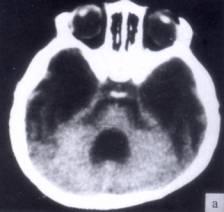

病历摘要:??患者女性,10岁。结核性脑膜炎愈后8月,头痛伴恶心呕吐1周,并渐加重。体检:神清,精神差,反应迟钝,双眼底视神经乳头水肿,双眼外展差,余未见...

问题 病历摘要:??患者女性,10岁。结核性脑膜炎愈后8月,头痛伴恶心呕吐1周,并渐加重。体检:神清,精神差,反应迟钝,双眼底视神经乳头水肿,双眼外展差,余未见明显异常。 目前治疗脑积水的措施包括下列哪些?